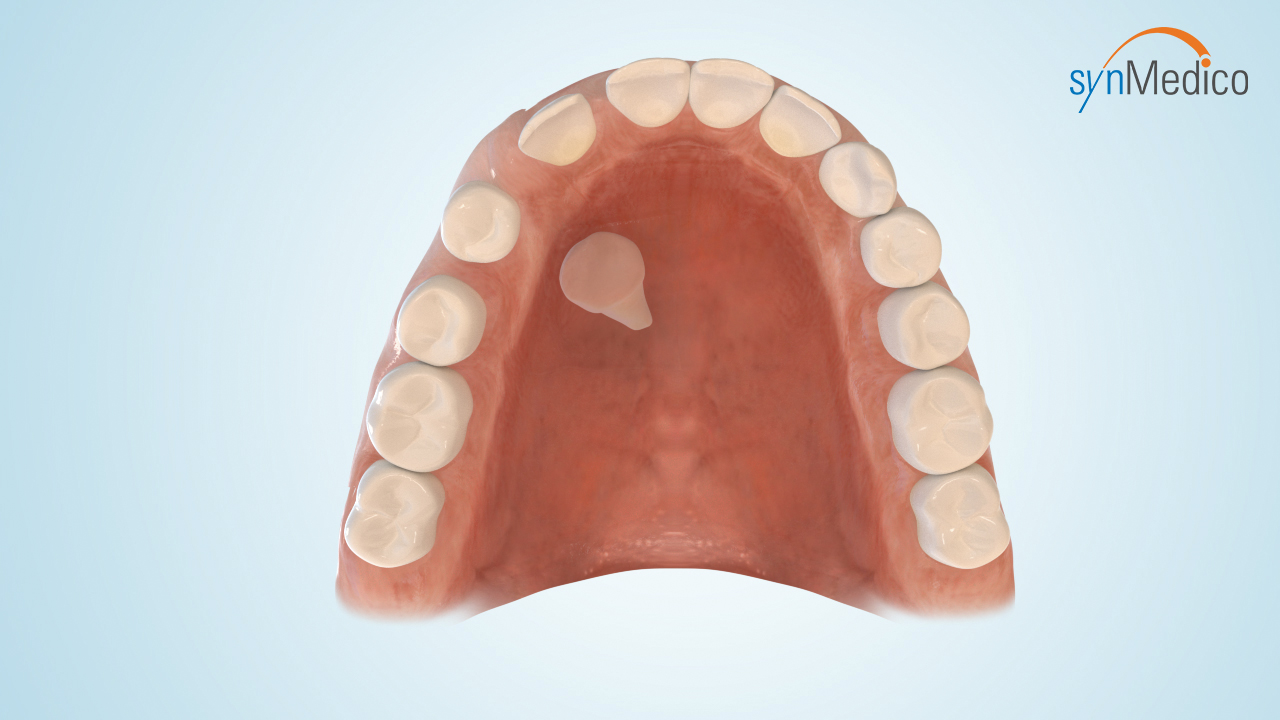

Freilegung von Zähnen

Gelegentlich verbleiben Zähne in der Wachstumsphase im Kiefer, da eine Blockade durch Nachbarzähne den Durchtritt verhindert. Durch eine kombinierte Behandlung mit den Techniken der Kieferorthopäde und der Kieferchirurgie können solche Zähne in die Zahnreihe eingestellt werden.